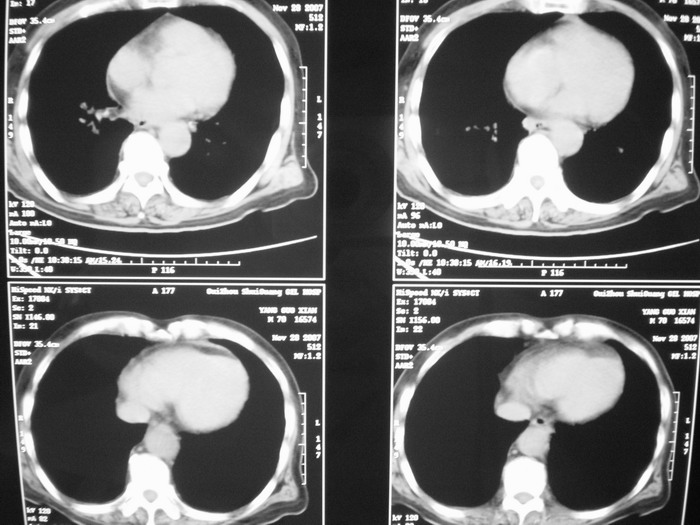

m、70y,反复咳嗽2月。请各位同仁给定位1、(肺?,纵隔?)2、定性。感谢!!

右后纵隔占位,气管前腔静脉后淋巴结肿大:1.神经源性肿瘤,2.恶性淋巴瘤?

右下肺纵隔旁较大 均匀密度肿块,部分边缘植入纵隔,气管明显受压 变形。支持:后纵隔肿瘤!首选:神经源性!不支持肺内肿瘤原因:1 肿瘤位于下叶支气管及背段支气管开口区,但未侵犯支气管,只是受压表现。2 纵隔内未见肿大淋巴结。3 肺内未见阻塞性肺炎。

考虑奇静脉食管隐窝战位,肺癌并纵隔淋巴转移

肺上有多个小结节哦,考虑转移,那就应该是恶性的啊